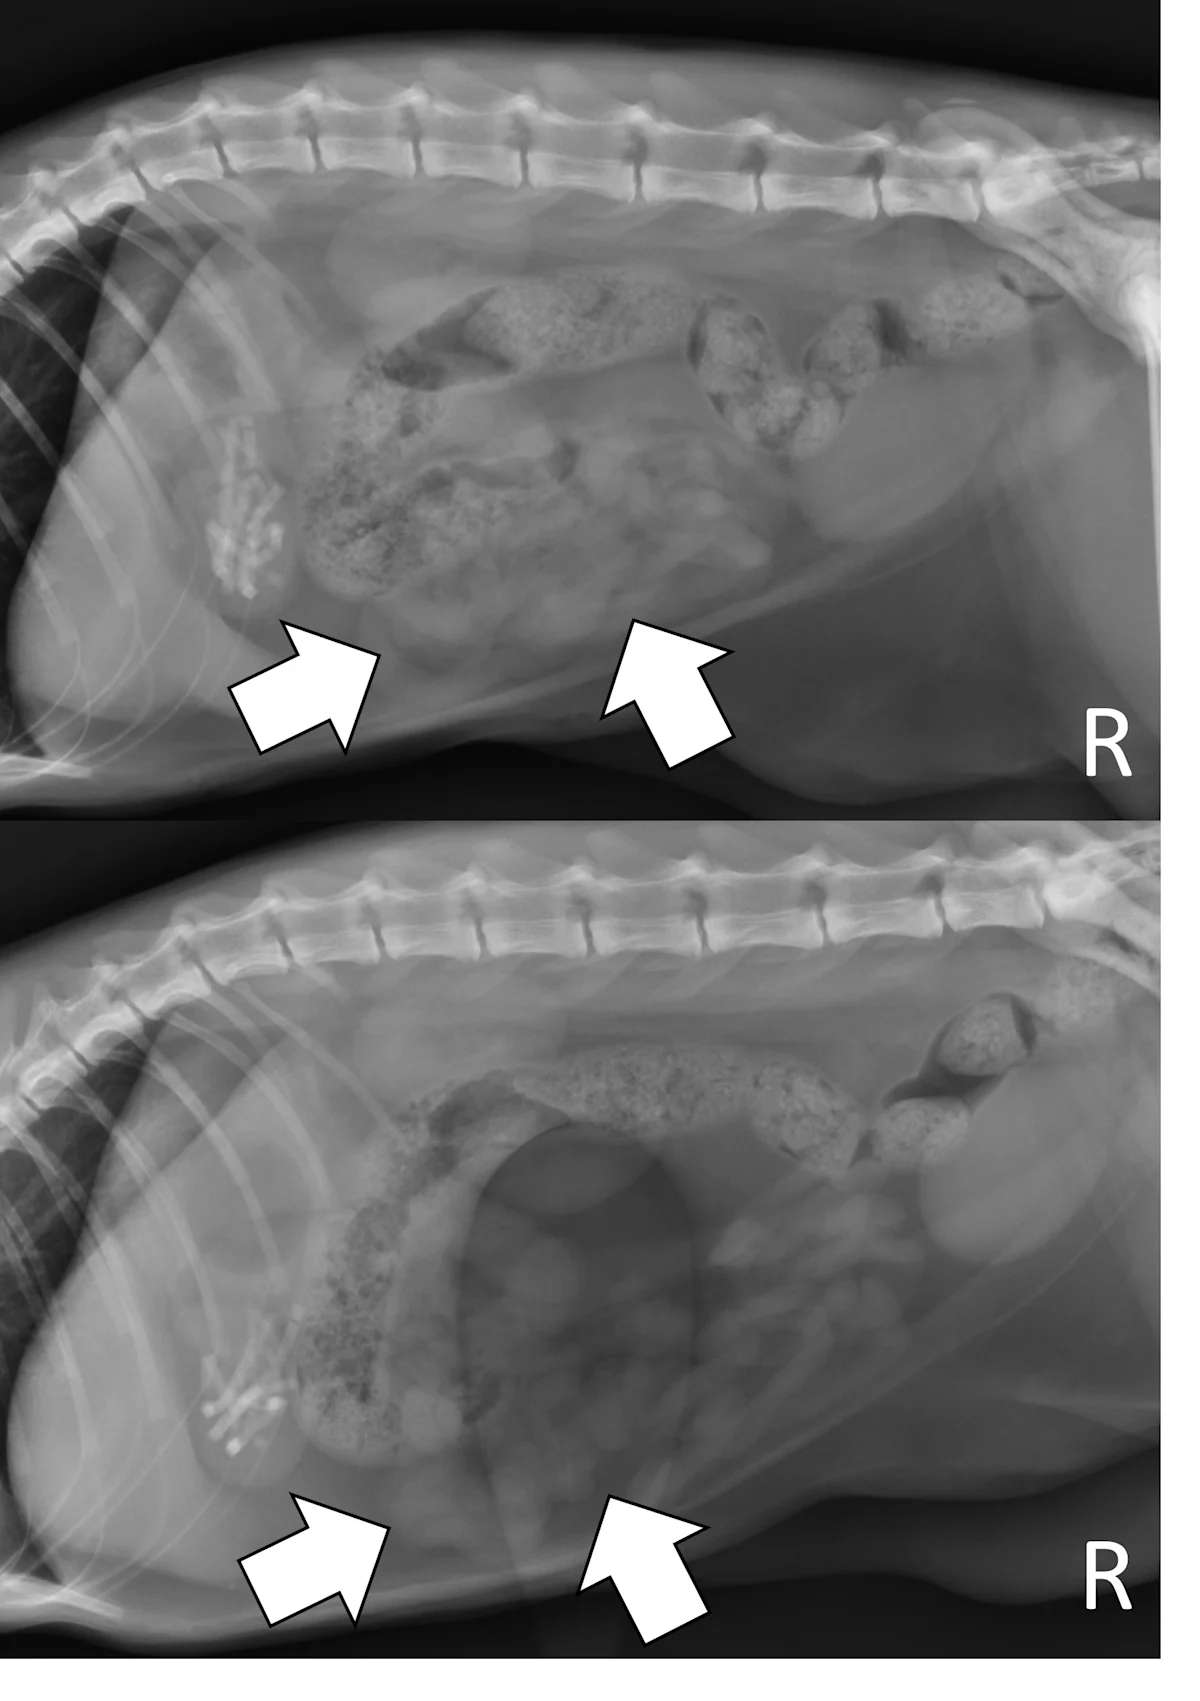

Right lateral and ventrodorsal abdominal radiographs of a 2-year-old spayed Boston terrier with a chronic pyloric outflow obstruction secondary to a surgically confirmed foreign body in the proximal duodenum. The stomach is severely dilated, predominantly with fluid (pound signs). Mineral opaque material located ventrally is consistent with a gravel sign (arrow).